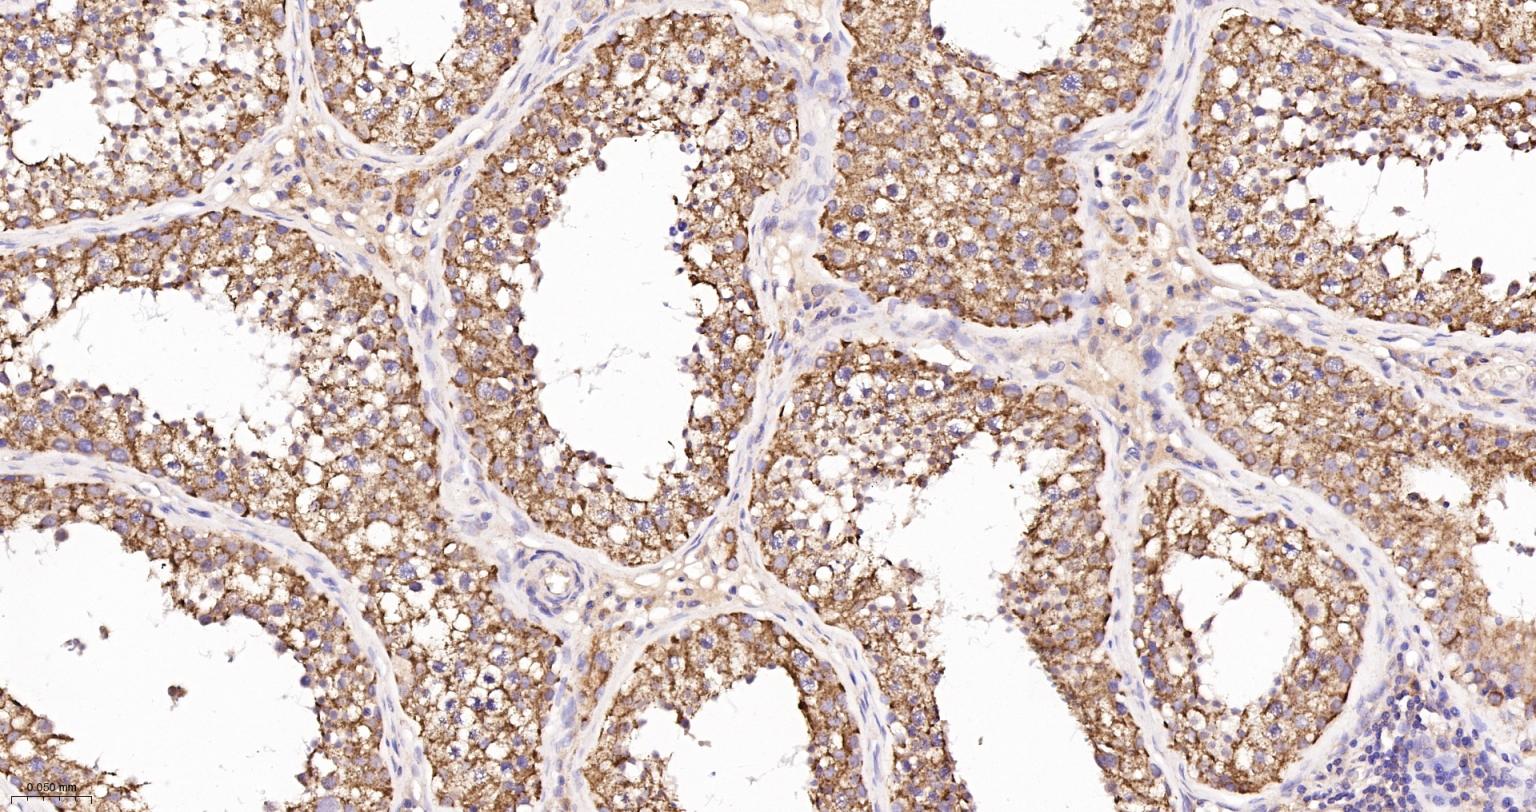

Paraformaldehyde-fixed, paraffin embedded Human Testicles; Antigen retrieval by boiling in sodium citrate buffer (pH6.0) for 15 min; Antibody incubation with AIF Monoclonal Antibody, Unconjugated(bsm-34316R) at 1:200 overnight at 4°C, followed by conjugation to the SP Kit(Rabbit, SP-0023) and DAB (C-0010) staining.